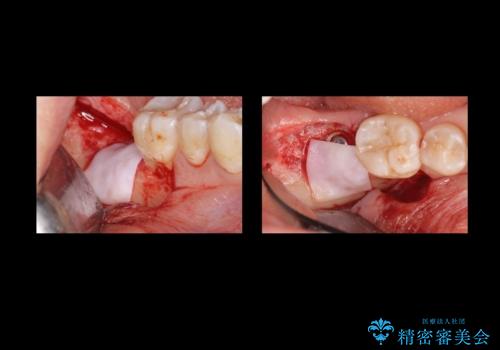

炎症で骨が少なかった場所には骨補填材を置いています。

高さがないため、スクリューリテインのインプラントの上部構造にしています。